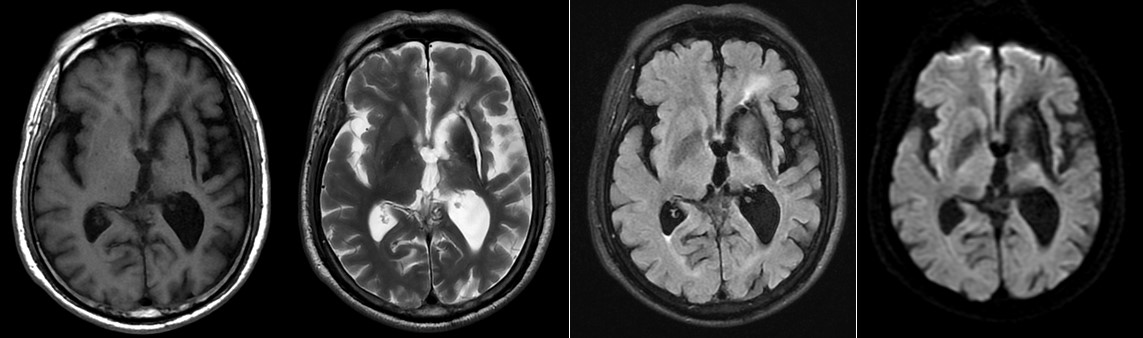

病例1 男,72y,既往脑梗病史,早晨突发双侧肢体无力,来院进行头颅MRI平扫+DWI检查,排查是否有新发脑梗。图像如下:

完成头颅常规检查后,看到左侧基底节区的软化灶,没有发现新发病灶,加做了头颅常规血管成像(3D-TOF MRA)。如下:

患者头颅MRA显示右侧颈内动脉及大脑中动脉完全闭塞,左侧颈内动脉狭窄,大脑中动脉未显影。立即往下扫描了颈部 MRA,颈部MRA显示右侧颈内动脉闭塞(绿箭),并在右侧颈外动脉多出了一个分支延伸至颅内(红箭),左侧颈内管腔狭窄(黄箭)。如此大面积的血管未显影,DWI上却未见新发病灶,病因是什么呢?